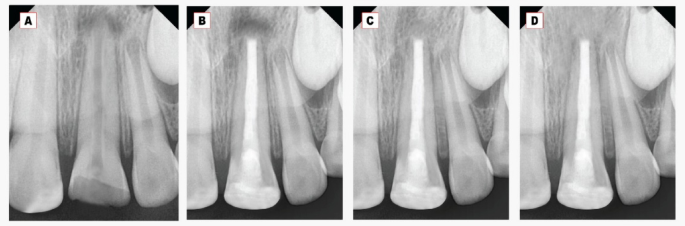

Regarding the periapical radiolucency (PAR) area, a significant decrease in the PAR area was found at all follow-ups within each group Figs. 2 and 3. At twelve months, the mean PAR area in the Well-Root PT group was (0.14 ± 0.08) compared to (2.3 ± 0.9) in the MTA group. A highly statistically significant difference was observed between the two tested groups at all follow-up periods (p < 0.001) as represented in Table 3.

Concerning the periapical bone radiodensity, there was a significant increase in the bone radiodensity at 6- and 12-month follow-up periods within each group, as shown in Table 3 and Figs. 2, 3. The mean periapical bone radiodensity in the Well-Root PT group was (178.2 ± 5.4) compared to (164.8 ± 9.4) in the MTA group at twelve-month follow-up. A highly statistically significant difference was found between the MTA and Well-Root PT groups at all follow-up periods (p < 0.001). Using the Bonferroni test, each observation was significantly different from the baseline and the other observation (p < 0.001).